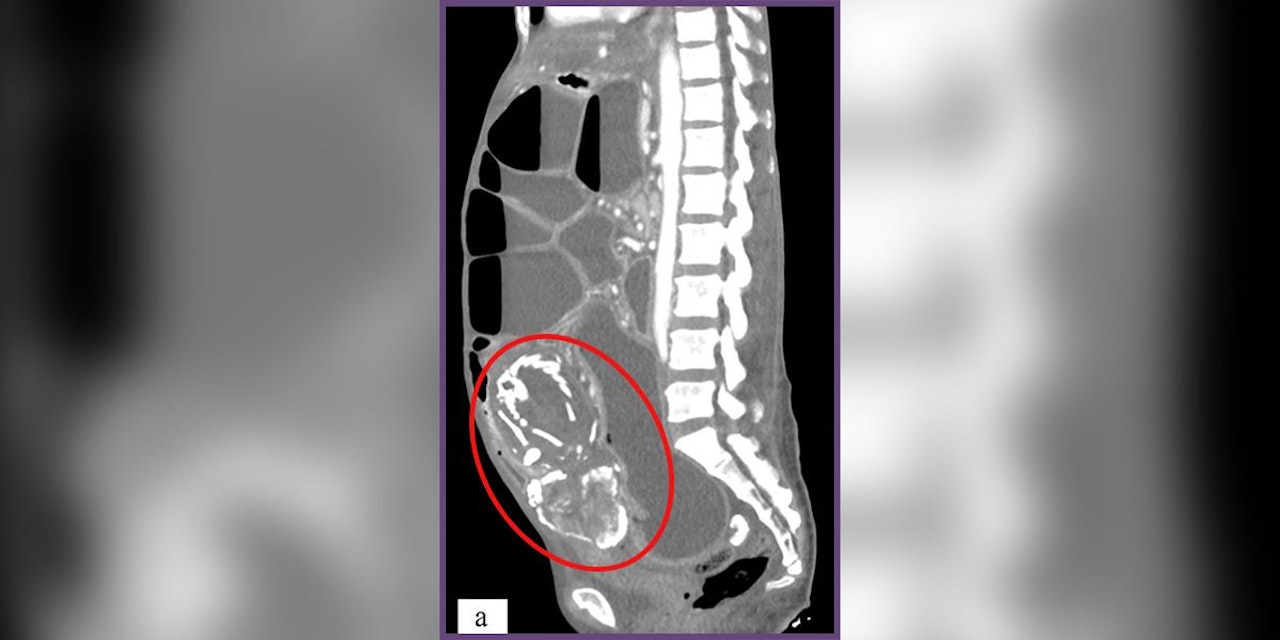

Die ursprünglich aus dem Kongo stammende 50-jährige Frau war als Flüchtling in die USA gekommen. Sie suchte Ärzte in New York auf und klagte über Magenkrämpfe, Verdauungsstörungen und ein gurgelndes Geräusch nach dem Essen in ihrem Bauch. Die Untersuchungen ergaben bald, dass ein toter, 28 Wochen alter Fötus – ein sogenanntes "Steinbaby" (Lithopädion) – in ihrem Unterbauch steckte und auf ihren Darm drückte. Das konnte auf eine schiefgegangene Fehlgeburt neun Jahre zuvor zurückgeführt werden. Ihr Fall wurde im Journal of Medical Case Reports dokumentiert.